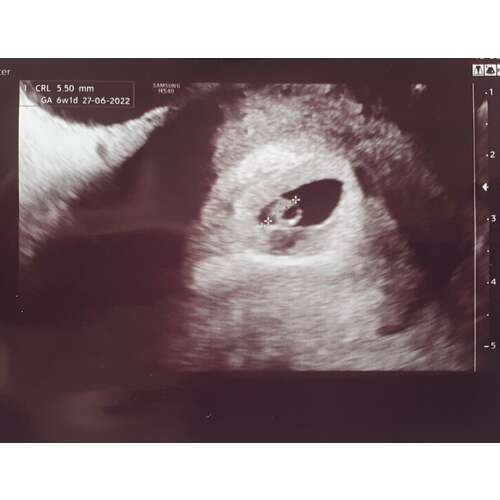

6 weken en 3 dagen! Ook kloppend hartje. Komt idd ook wel overeen 🥰

Ik had vandaag ook een goede echo met 6 wk!! Super opgelucht voor nu 😊

Yes!!! Gefeliciteerd 😍 Super blij voor jou! Heb je een foto? Ik moet morgen weer, ben dan rond de 8 weken, ben heel benieuwd!